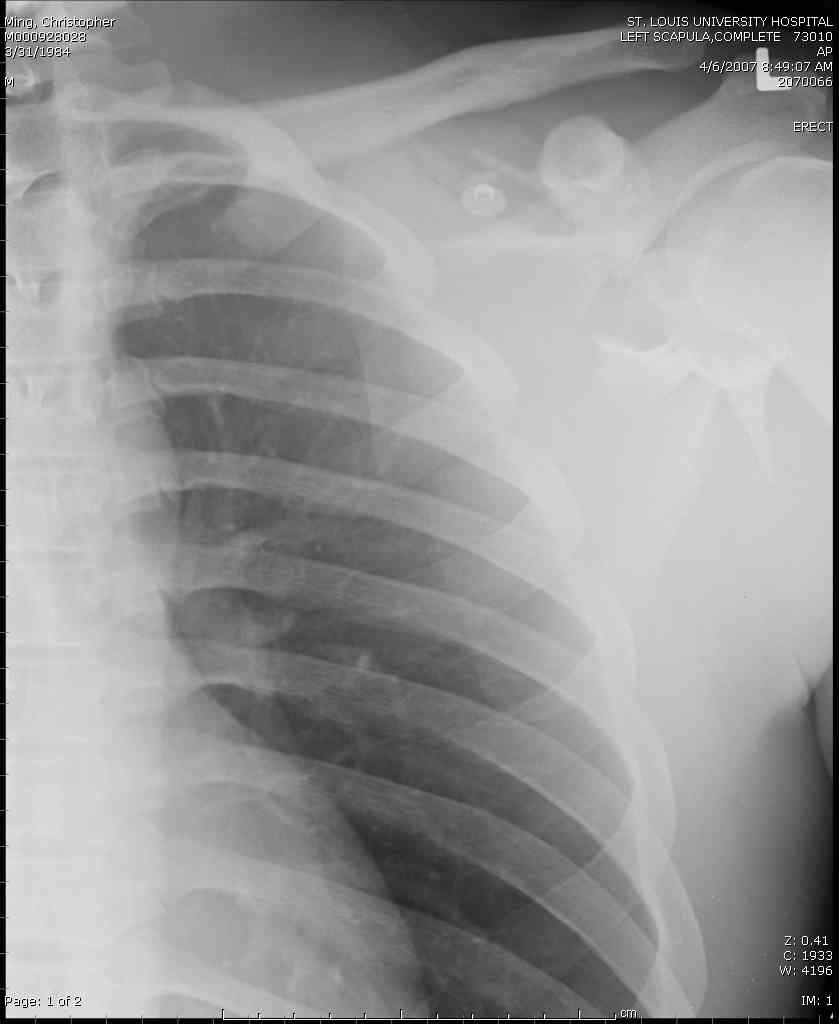

дравствуйте, коллеги. Мужчина 24 лет. Сегодня был прооперирован по Сушко-Илизарову (давно порывался, наконец-то руки дошли :)) На снимке перелом угла лопатки. Довольно крупный размер осколка. Следует ли оперировать такой перелом?Если есть резон оперативного лечения, то каким образом? (рекон. пластина, закрыто пришпилить спицами, винтами). ЭОПа в наличии нет. В области лопатки массивный отек мягких тканей. С уважением, Заднепровский Никита Николаевич

Для решения насчет оперативного вмещательства на лопатке сперва надо определиться с обьязательными ренгенологическими исследованиями, не менее трех стандартных проекций: прямая, аксиллярная и в позиции виде “Y”.

Прямую снимают под углом в 35 градусов от центра и вид “Y” в 90 градусов к нему. Несмотря на неудобства, больному необходимо сделать

аксиллярный снимок.

К-томографические и Трехмерные(3D)снимки крайне важны для определения внутрисуставных переломов и классификации.

Кроме анатомической классификации, переломы лопатки делятся на стабильные и нестабильные, внутри- и внесуставные и с вовлечением суставной поверхности.

Нестабильные внесуставные переломы лопатки типично сочетаются с переломами ключицы и ребер.